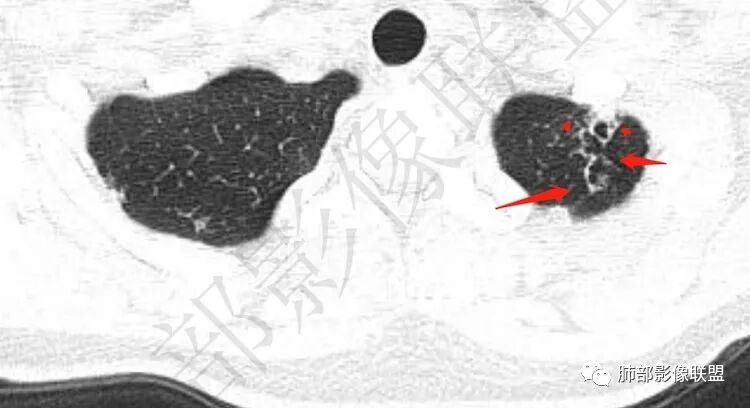

两肺多发囊或空洞(部分腔内不干净可见间隔影)+多发结节 (右侧胸膜下的结节显著)+左肺尖斑片影。年轻女性,体检发现。考虑结核?鉴别PLCH(奇异囊加结节,吸烟男性多见),转移瘤(要有原发肿瘤病史)

中年女性,体检发现, 双肺上叶多发囊腔伴斑点,斑片影,囊腔壁不规则,部分内见分隔,部分可见树芽征。考虑感染性病变,结核,NTM可能。

慎独:

中年女性,体检发现, 双肺上叶多发囊腔伴斑点,斑片影,囊腔壁不规则,部分内见分隔,部分可见树芽征。考虑感染性病变,结核,NTM可能;建议密切随访左上肺胸膜下囊性灶。

年轻女性,血常规正常,体检发现,影像表现:双上肺多发空洞及空腔样改变,薄壁为主,部分壁不规则,伴不规则分隔,疑似鬼脸征,多数位于胸膜下。诊断:1、隐球,年轻女性,体检发现,血常规正常,多数胸膜下,疑似鬼脸征,必须首先考虑。2、结核,发病部位支持,多发空洞样病变支持,但无临床症状,病灶形态太单一,无树芽征,可能性不大。3、PLCH,无吸烟史,无临床症状,可能性小。4、寄生虫,无嗜酸增高,无IGE增高,可能小,5、空腔性转移,无原发灶,年轻较小,暂不支持。6、多中心原发腺癌,空腔周围无明确边界清楚的GGO,年轻。可能小。7、NTM,无支扩,可能小。8、风湿类疾病,无相关病史,无相关自身抗体结果,暂不支持。综上,考虑隐球菌可能大。先查隐球荚膜抗原。必要时穿刺活检。

2.双肺多发薄壁空洞影、条索影及结节影,边界较清楚,密度偏高不柔和,散乱,但有成簇倾向或堆积感,胸膜下分布为主,双肺上叶分布为主。

3.空洞相当不规则,缺乏张力,未见血管穿行,未见壁结节,未见液平。

1.年轻女性,缺乏临床表现,多发空洞及结节影、条索影,上肺胸膜下分布为主,临床实践中常见肺病是什么?正如部分老师分析的—继发性肺结核!